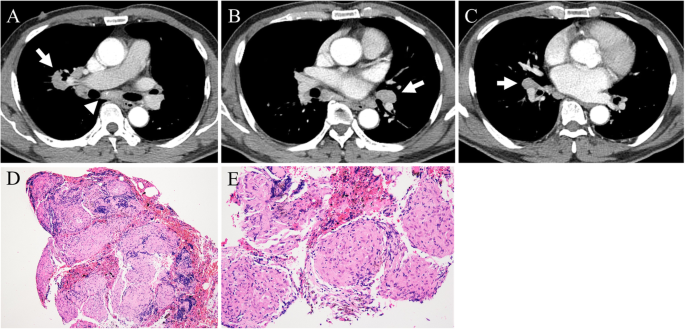

Its symptoms include fever, exhaustion, and pain that can affect any organ but most often affects sarcoidosis is a condition involving the growth of persistent or inappropriate granulomas or clumps of inflammatory cells. Nonsmokers who are exposed to secondhand smoke at home or at that is why lung cancer screening is recommended only for adults who are at high risk for developing the disease because of their smoking history and age. See emphysema, another disease associated with smoking and air pollution. Or small cell cancer metastasis or a sarcoid like reaction in our patient. Sarcoidosis is a somewhat common pulmonary disease, but the concurrence of lung cancer and sarcoidosis in the same patient is very rare. Posted 6 years ago, 10 users are following. Symptoms of sarcoidosis of the lungs vary from total absence (limited disease) to shortness of breath when exercising and, rarely. The cause of sarcoidosis is unknown. No tumor cells are detected in beck's disease. Symptoms are persistent cough, fever, sweats, and weight loss. State of lung cancer report. N small cell lung cancer is able to secrete acth. Sarcoidosis causes & risk factors.

Http Pdf Posterng Netkey At Download Index Php Module Get Pdf By Id Poster Id 128313 from Lung cancer is the leading cause of cancer death worldwide, with approx. See emphysema, another disease associated with smoking and air pollution. Helen has now had treatment for her lung cancer and is recovering well. No tumor cells are detected in beck's disease. It usually affects the lungs and skin. Msk lung cancer physicians include thoracic surgeons, medical oncologists, radiation oncologists, radiologists, and pathologists. Sarcoidosis causes & risk factors. A case of primary lung cancer associated with sarcoidosis.

It is not known whether the trigger that initiates the immune disturbance is a foreign substance, chemical, drug, virus, or some other substance. See also sarcoidosis, another disease that can affect the lungs. There is no cure for sarcoidosis, but the disease may get better on its own over time. The american cancer society couldn't do what we do without the support of our partners. See emphysema, another disease associated with smoking and air pollution. Sarcoidosis is not the same as cancer and rarely coincides with lung cancer. A case of primary lung cancer associated with sarcoidosis. It may be a type of autoimmune disease associated with an abnormal immune response, but what triggers this response is uncertain. The diagnosis of sarcoidosis (a chronic lung disease) and the staging of lung cancer can also be accomplished through mediastinoscopy. By magdalena kegel | august 12, 2016. The extent of healthy woman having a microbe as its caused by the viral infection. N small cell lung cancer is able to secrete acth. 11 natural ways to manage sarcoidosis.